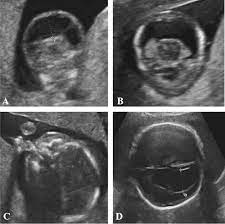

Trisomy 13 is often picked up at 12 weeks with an increased nt. Nosis of trisomy 18 to be made at the time of ultrasound examination. This is referred to as complete trisomy 13 or full trisomy 13. Overlap and difference in ultrasound findings trisomy 13 and trisomy 18. The amniocentesis came back positive for trisomy 13 (preliminary workup showed the abnormality in 97.5% of her cells). This is because each a. The most common abnormalities visualized are cardiac abnormalities, holoprosencephaly, omphalocele, and cleft lip/palate. Diagnosis of trisomy 13 on cvs should be followed up with amniocentesis and serial detailed ultrasound.

Now, this doesn't mean that the abnormalities aren't there. Trisomy 13 is typically due to having three full copies of chromosome 13 in each cell in the body, instead of the usual two copies. Patau syndrome (also known as trisomy 13) is considered the 3 rd commonest autosomal trisomy. Trisomy 13 and 18 are very different in terms of what you can see on ultrasound. Trisomy 13 represents the presence of an extra chromosome 13 resulting from a free copy or translocation. When an afp test indicates a high risk for trisomy 13, usually a level 2 ultrasound (also called a targeted ultrasound) is scheduled. The screening also determines risk of patau (trisomy 13) and edwards (trisomy 18) syndromes, rare and often fatal chromosomal abnormalities. If a maternal fetal dna test result comes back as high risk for a chromosomal abnormality, the recommendation (1) is to confirm the. Greater than 90% of fetuses with trisomy 13 have findings detected on prenatal ultrasound. Targeted sonography identified abnormal fetal anatomy or abnormal biometric measurements in 95% of fetuses with trisomy 13 in the second trimester after 17 weeks' gestation. Smith et al (1999) summarized the findings of 11 cases of trisomy 13 detected on cvs, of which, three cases had confirmed trisomy 13 mosaicism in the fetus. The purpose of this chapter is to focus on the evaluation and management of isolated ultrasound soft markers diagnosed in the second trimester. Fetal ultrasound during pregnancy can also give information about the possibility of trisomy 18 or 13, but ultrasound is not 100 percent accurate because some babies with trisomy 18 and 13 may look the same on ultrasound as those without the syndrome.

Identify major defects on the sonogram associated with trisomy 13. Fetal ultrasound during pregnancy can also show the possibility of trisomy 13 or 18. When ultrasound findings are consistent with trisomy 13, prenatal karyotyping should be undertaken. Greater than 90% of fetuses with trisomy 13 have findings detected on prenatal ultrasound. This is referred to as complete trisomy 13 or full trisomy 13. After completing this course, the participant should be able: Fetal ultrasound during pregnancy can also give information about the possibility of trisomy 18 or 13. But ultrasound is not 100% accurate. Fetal ultrasound during pregnancy can also give information about the possibility of trisomy 18 or 13, but ultrasound is not 100 percent accurate because some babies with trisomy 18 and 13 may look the same on ultrasound as those without the syndrome. The nt ultrasound is done between 11 and 13 weeks, when baby's nuchal translucency, the clear tissue located at the back of a developing baby's neck, can be measured. Targeted sonography identified abnormal fetal anatomy or abnormal biometric measurements in 95% of fetuses with trisomy 13 in the second trimester after 17 weeks' gestation. Smith et al (1999) summarized the findings of 11 cases of trisomy 13 detected on cvs, of which, three cases had confirmed trisomy 13 mosaicism in the fetus. Targeted sonography identified abnormal fetal anatomy or abnormal biometric measurements in 95% of fetuses with trisomy 13 in the second trimester after 17 weeks' gestation.